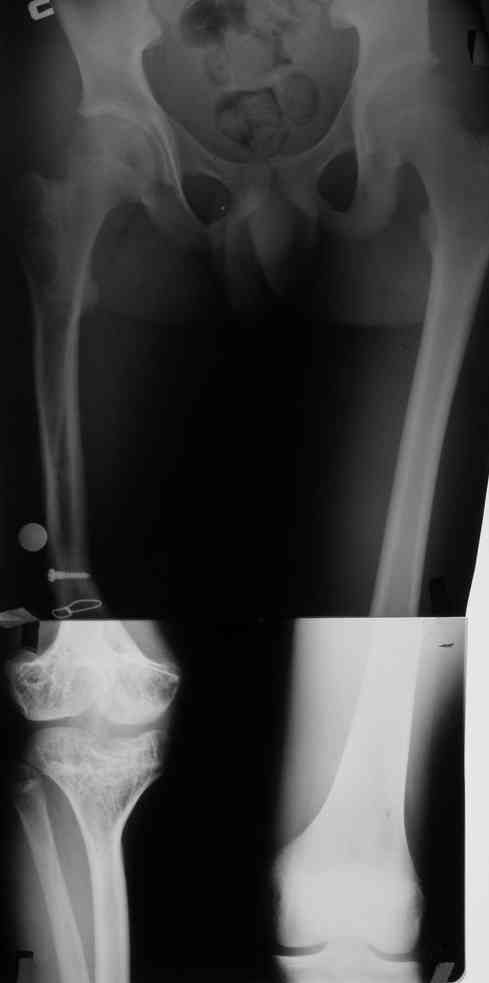

Фиброзная дисплазия бедра, укорочение 12 см.

Несколько лет нами наблюдается пациент с фиброзной дисплазией бедра (сейчас ему 18 лет).

В анамнезе 2 операции: 1.корригирующая остеотомия бедра с резекцией и аутопластикой на месте псевдоартроза бедра в н/3. 2.кортикотомия, дистракционный остеосинтез бедра в аппарате. Последний аппарат находился на больном 1г 3мес и еще 1 год ношения ортеза в связи с замедленной консолидацией.

Сейчас ортопед. укорочение конечности составляет 12 см (7 см-бедро и 5 см-голень)Движения в коленном суставе после удлинения 180-130.Удлинение бедра рикованно и грозит несращением и стойкой контрактурой колена.

Спасибо за ответы. Это рентгенограммы пациента до и после последнего удлинения бедра

Уважаемый Анатолий! Рост пациента с фиброзной дисплазией бедра примерно 160 см. Но укорочение контралатеральной конечности мы не хотели бы делать.